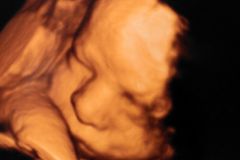

A petition launched by the Society for the Protection of Unborn Children is calling upon the Health Secretary to tackle coercive abortion.